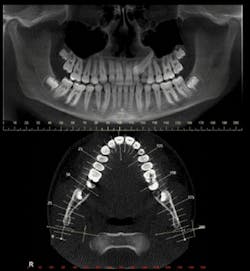

A common orthogonal cut is the panoramic planing. (see Figure 5). The panoramic plane can be formulated widely enough to include mandibular-maxillary complex, or either arch can be selected by a thinner cut which shows a more accurate virtual representation.